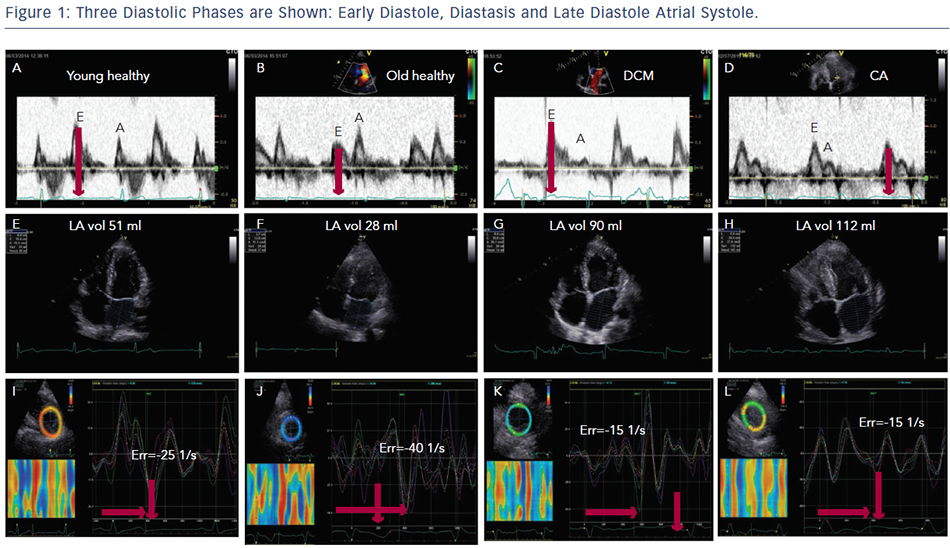

Diastole is an important period in the cardiac cycle when all heart components integrate together to secure optimum ventricular filling which determinImage titlees the stroke volume pumped by the ventricle in the succeeding cycle. Three diastolic phases are well-recognised; early diastole, diastasis and late diastole ‘atrial systole’ (Figure 1). To describe the actual events happening in the ventricle the three phases are named; early filling, diastasis and late filling.

With age, significant changes occur in diastolic function over and above those affecting systolic function. In the young up to the fourth decade of life, the left ventricle fills with a dominant early diastolic volume followed by a smaller late diastolic volume. The pronounced early diastolic phase is caused by the low (negative) apical pressures compared with those at the base of the LV, maintained by an apical untwist, anticlockwise rotation of the cardiac apex, (Figure 1A–C) which results in a suction effect. With progressive collagen deposition in the myocardium, in the fifth decade of life, its relaxation slows and is delayed. This results in prolongation of isovolumic relaxation time due to delayed opening of the mitral valve. This occurs in the overall diastolic period but especially in the early diastolic phase, (Figure 1B) and results in compromised early filling component (or volume) with a compensatory increase in the late diastolic component and a more pronounced apical untwist (Figure 1J).3 These changes are greater if there is additional pathology affecting the left ventricle e.g. coronary artery disease or systemic hypertension. In the worst cases, the early filling can be completely truncated and the left ventricle fills with an isolated late diastolic filling component. If such patients develop atrial fibrillation, the isolated late diastolic filling component will be shifted to early diastole but at the expense of raising the left atrial pressure and reducing the stroke volume.4,5